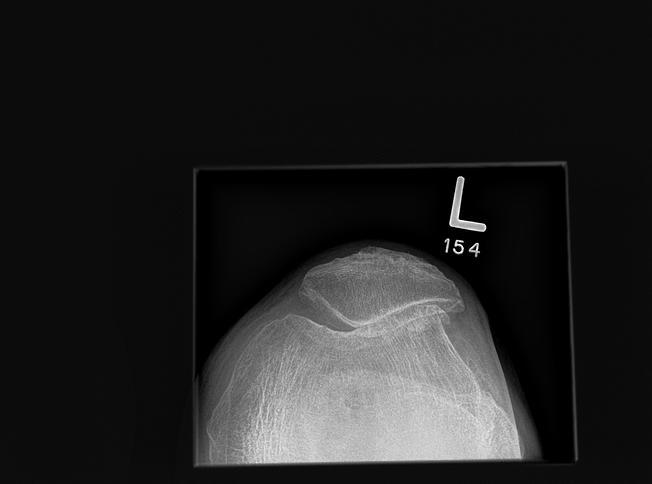

What does this x-ray show?

Skyline view OA of patellofemoral compartment: loss of joint space, osteophytes, subchondral sclerosis.